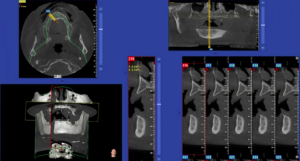

Authors: Daniele Benedetti Forastieri and Daniele Godi

It is now possible to introduce profound changes in case-specific difficulty/risk assessment processes by learning how to read three-dimensional (3D) data.After decades-long use of two-dimensional...

The aim of this study is to evaluate three-dimensionally the dental movement of impacted palatally canines, following an opercolectomy performed by laser. We also monitored patients with both digital...